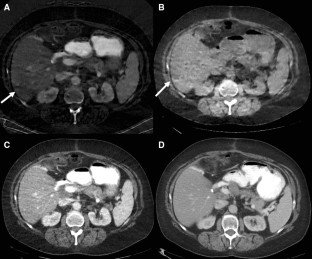

Fig. 1

Fig. 2

Fig. 3

Fig. 4